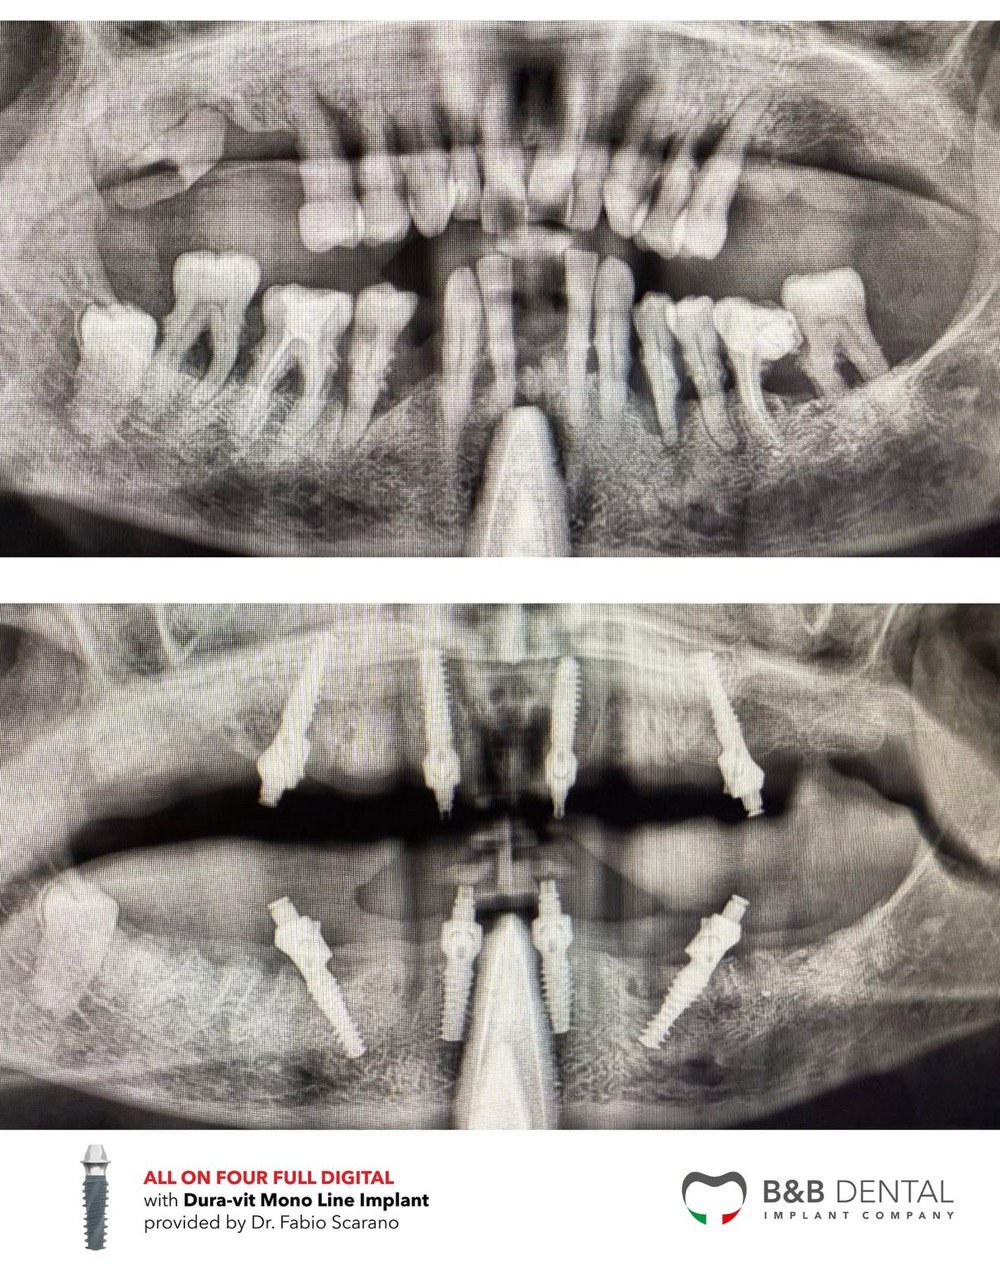

Данные пациента: Возраст: 51 год Пол: Женский Курильщик: Нет Патологии: нет Гигиеническое состояние: удовлетворительное Аллергия: нет

Лечение проведено с применением flapless-техники (бесклаптная техника) и полностью цифрового подхода: навигационная хирургия, протетическое проектирование на основе индивидуальных черт лица пациента и установление монокомпонентных имплантатов с интегрированными MUA (B&B Dental).